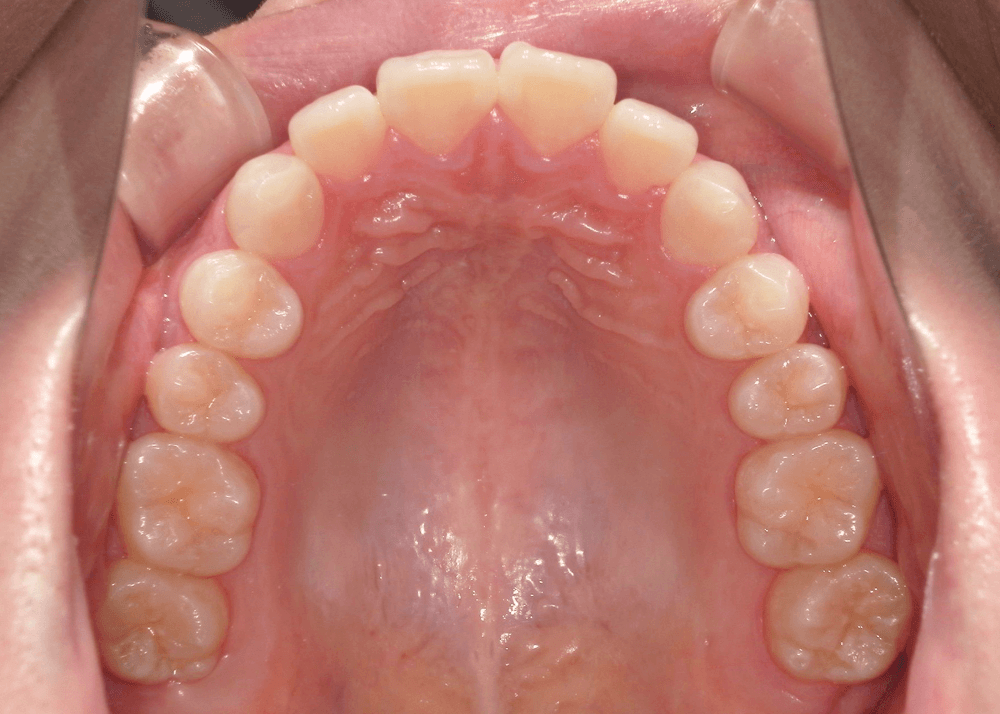

<初診時>

一見すると大きなガタガタはなく、歯並び自体は比較的きれいに整っているように見えます。

角度を変えて確認すると、上の前歯が前方に突出しており、上下の前歯がしっかり噛み合っていない状態(前歯部に隙間)が認められました。

このように、歯列の乱れは軽度である一方、前歯の前突および口元の突出感が認められました。

綺麗に噛み合うためには、上下の歯の大きさのバランスも重要な要素の一つです。本症例では、上の歯がやや大きく、そのまま並べると噛み合わない状態でした。